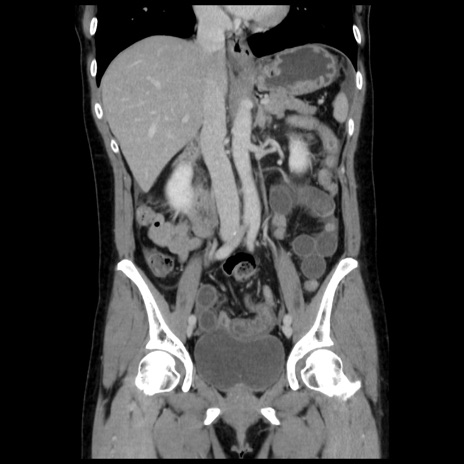

症例10(冠状断像)

【症例】 50歳代女性

【主訴】 腹痛

【現病歴】前日生レバーを食べた。今朝に排便あり。 昼前に突然発症の腹痛を生じ、当院救急外来を受診した。

【既往歴】 子宮筋腫にてで子宮全摘後

【身体所見】 意識清明、腹部:平坦、軟、下腹部やや左を中心に圧痛・反跳痛あり、筋性防御あり

【データ】WBC 7800、CRP 0.07